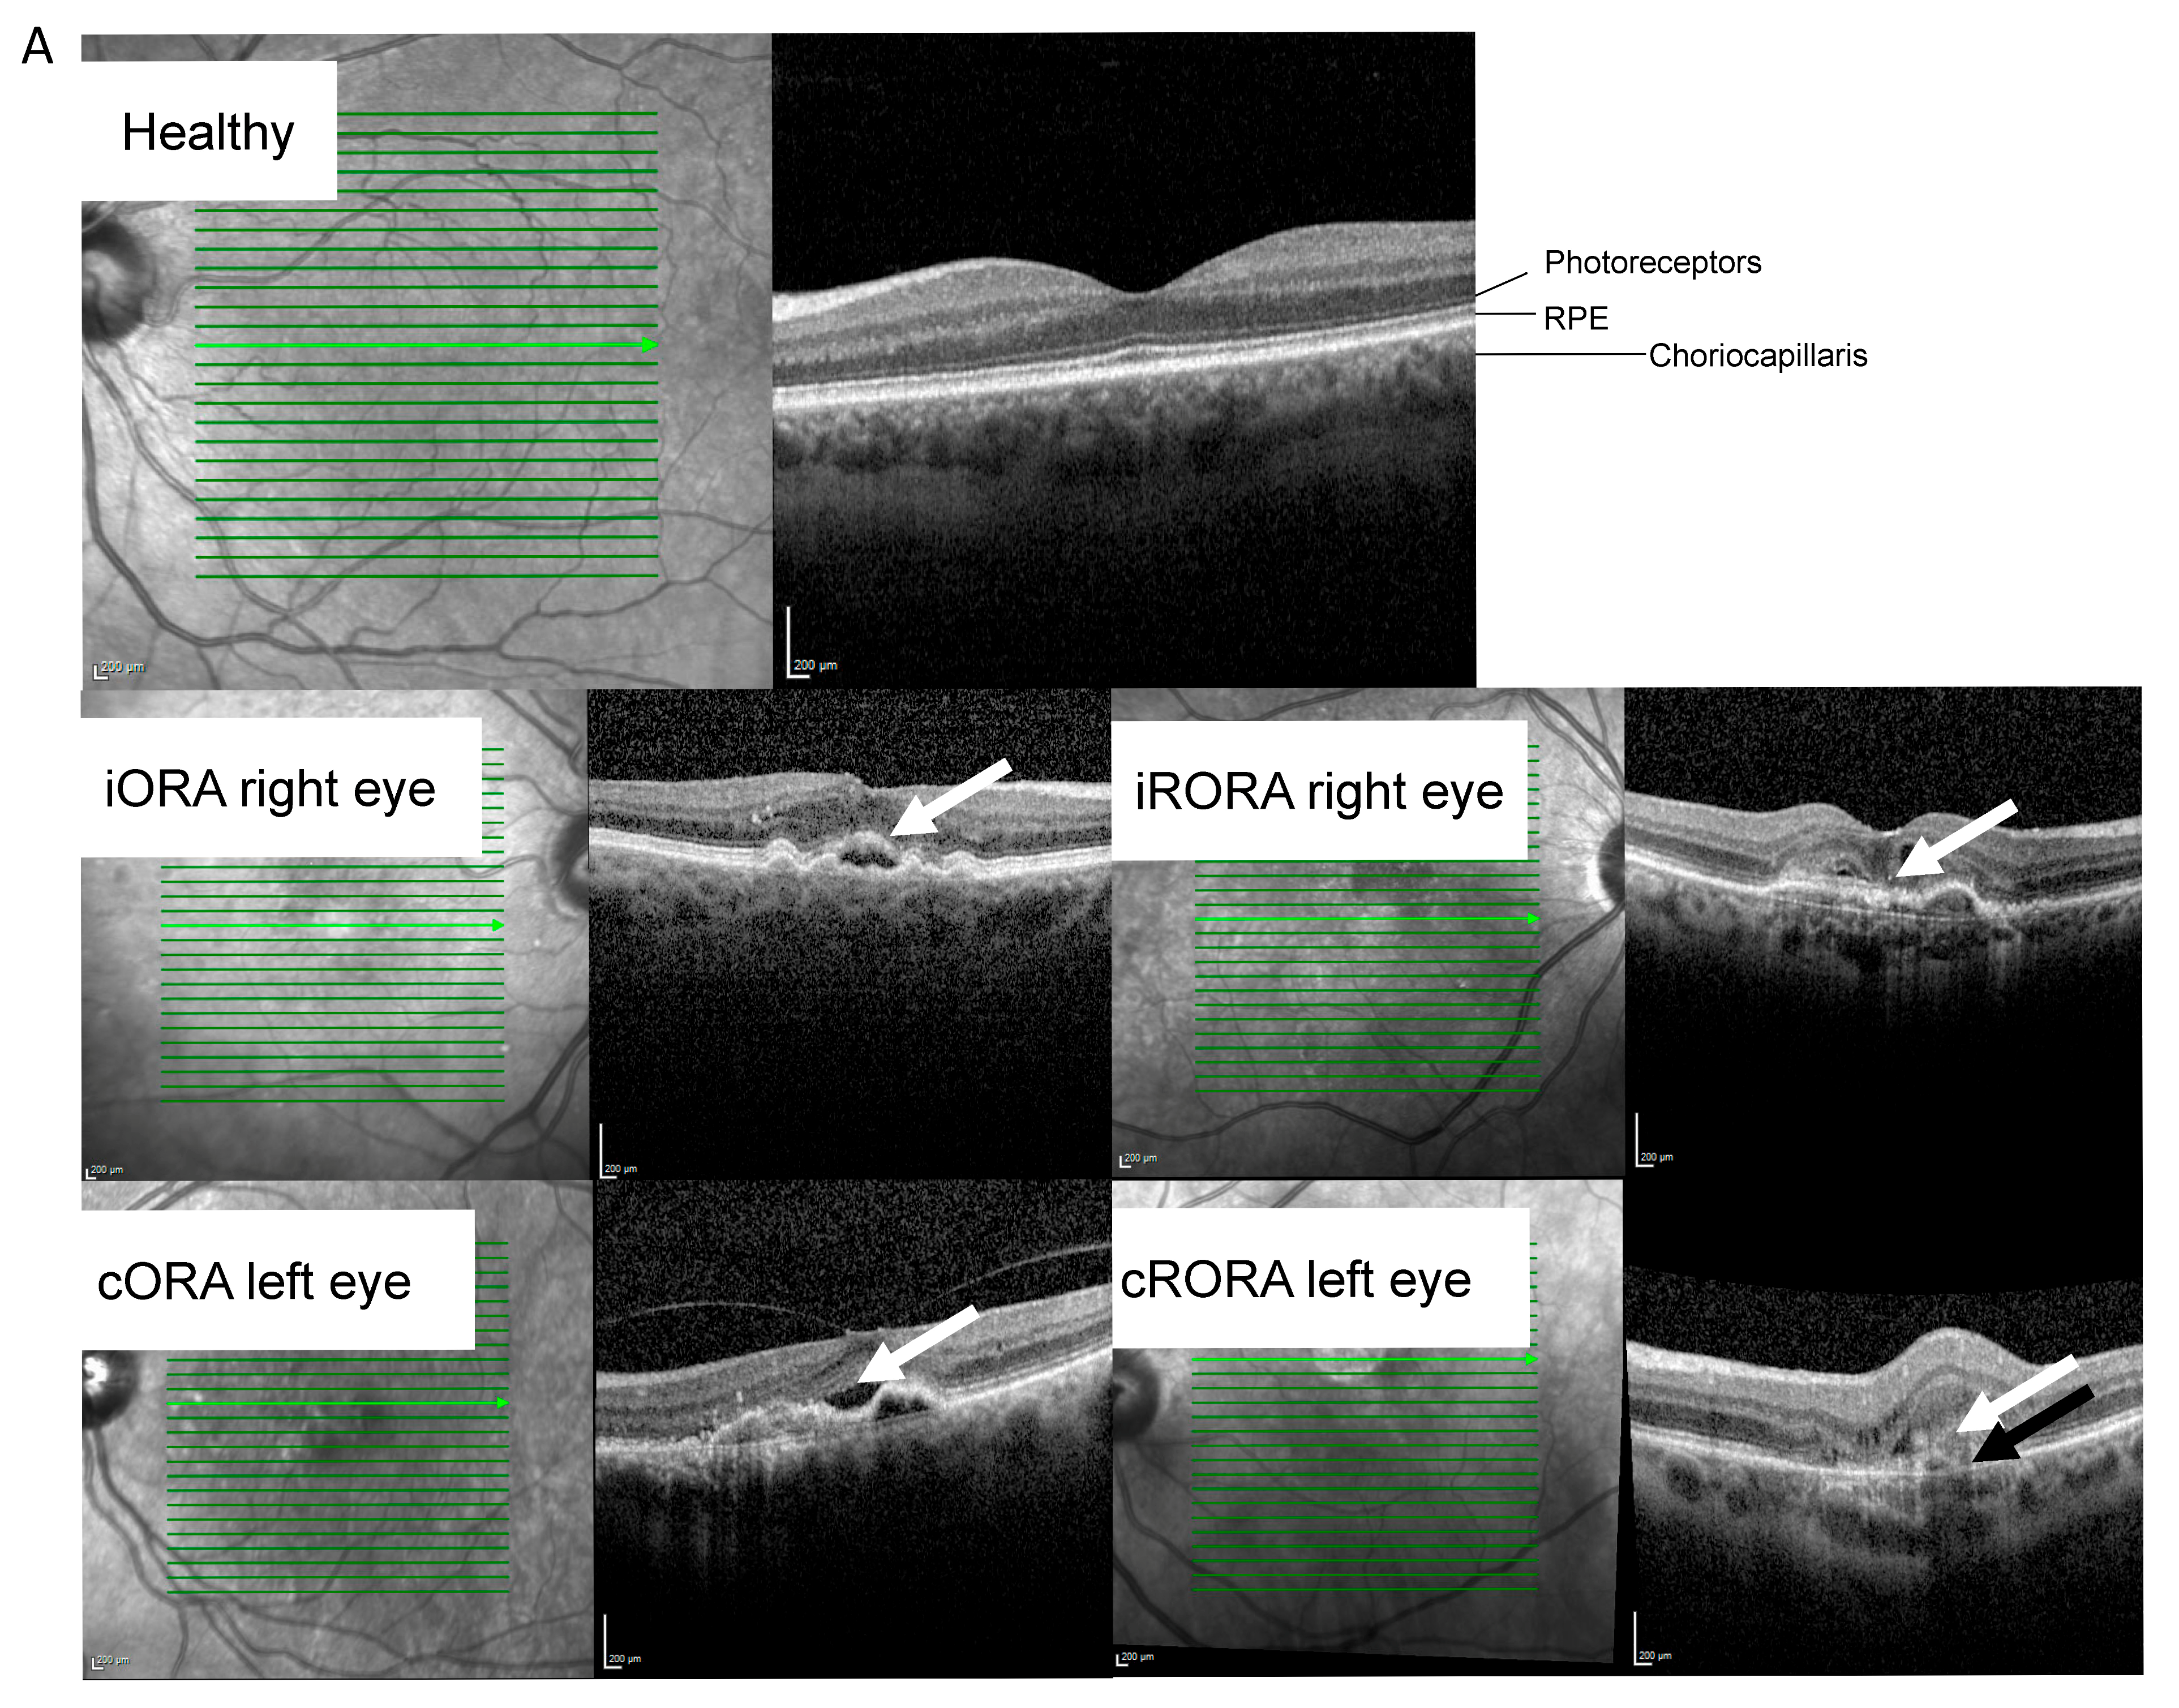

2.2. RNA Profile Linked to nAMD Progression

| Retinal atrophy at sampling. n (iORA/cORA/iRORA/cRORA/RPE tear/unknown) | 11/12/12/17/6/2 | |||||||||

| Fluid status at sampling. n (IRF/SRF/IRF & SRF/unknown) | 18/21/18/3 | |||||||||